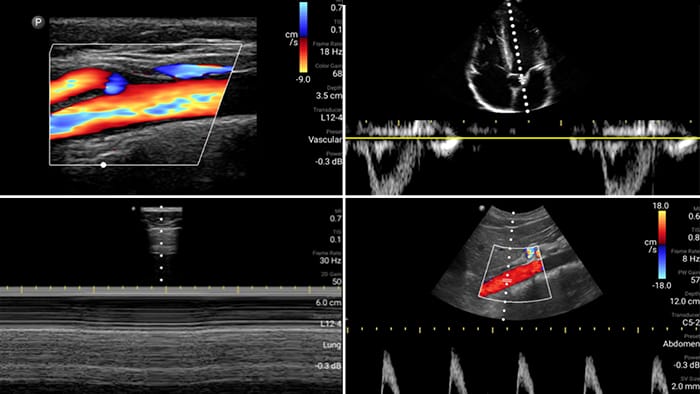

Evaluate, diagnose and treat your patients in minutes with a multi-point POCUS exam.

Lumify can help assess patients faster and improve accuracy when diagnosing common causes of dyspnea and other lung conditions.

Every second counts in cardiac care

Heart attack patients need immediate care. Lumify's cardiac presets can help patients get diagnosed faster to improve their outcomes.

• 4 to 1 MHz extended operating frequency range • 2D, color Doppler, M-mode, advanced XRES and multivariate harmonic imaging • High-resolution imaging for abdominal and cardiac applications: Cardiac, OB/GYN, Lung, Abdomen and FAST imaging preset optimizations Lumify aids life-saving technology in prehospital setting